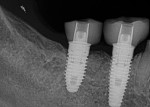

Stage 3 involved screw-retained hybrid abutment crowns on implant Nos. 30 and 31 with an e.max crown on tooth No. 29.7 The provisional restoration on implant Nos. 30 and 31 was removed and images of the soft tissue coronal to the implants were taken to capture the contours for designing the proper emergence profile of the final restorations. Two ScanPosts were placed into the implants, and full seating was confirmed radiographically (Figure 11). An appropriate ScanBody was seated over the ScanPost specific to the implant system and diameter, to digitally transfer the exact position of the hex on the integrated implant. Tooth No. 29 was prepared according to biomechanical principles and tissue packed with No. 00 and No. 2 retraction cords.

Once milled, the fit of the two implant-supported restorations onto their TiBases (Dentsply Sirona) was confirmed. After oven crystallization and cooling, the implant-supported crowns were adhered to their TiBases with Multilink® Cement (Ivoclar Vivadent) to fabricate the screw-retained hybrid crowns for implant Nos. 30 and 31. They were hand torqued into implant Nos. 30 and 31; seating was confirmed radiographically (Figure 12). The hybrid abutment crowns were then torqued into place to 35 Ncm. Following a 10-minute wait, the screws were torqued again to 35 Ncm, with an awareness of the stretch of screw mechanics.8 Teflon tape was placed over the screw heads for protection and hybrid abutment crown access openings were sealed with shade A1 dentin Empress composite.